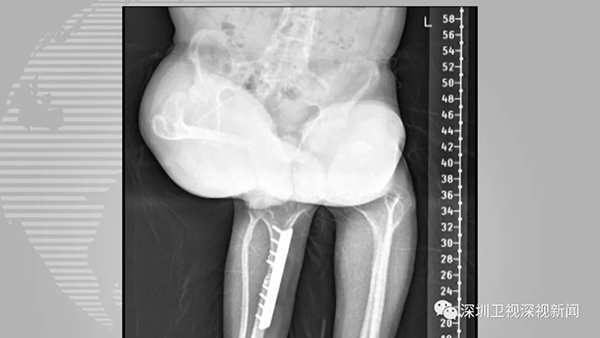

陈建文介绍,医学上膝关节屈曲挛缩成60度角已是重度畸形,而赵能康达到90多度,已属于极重度畸形。而长时间的极重度畸形导致血管、神经短缩,使得手术风险极高、难度极大——如果伤到重要神经,有可能出现下肢瘫痪,如果伤及下肢大血管,有可能出现下肢坏死。

“普通矫形手术已没法解决赵能康的问题,综合考虑后,我们主要运用牵张组织再生技术,在手术的同时给他的腿部装上机器人外架。”陈建文向记者介绍,“通过精密计算,外架能逐渐矫正膝关节屈曲畸形并辅助血管、神经再生,让治疗更精准、可控。”

经过4个月的3次手术,治疗效果明显,赵能康的双腿均能伸直。医生为他拆除了机器人外架,并指导他积极锻炼双下肢的肌肉力量,赵能康在术后半个月完成了人生的第一次“直立行走”。